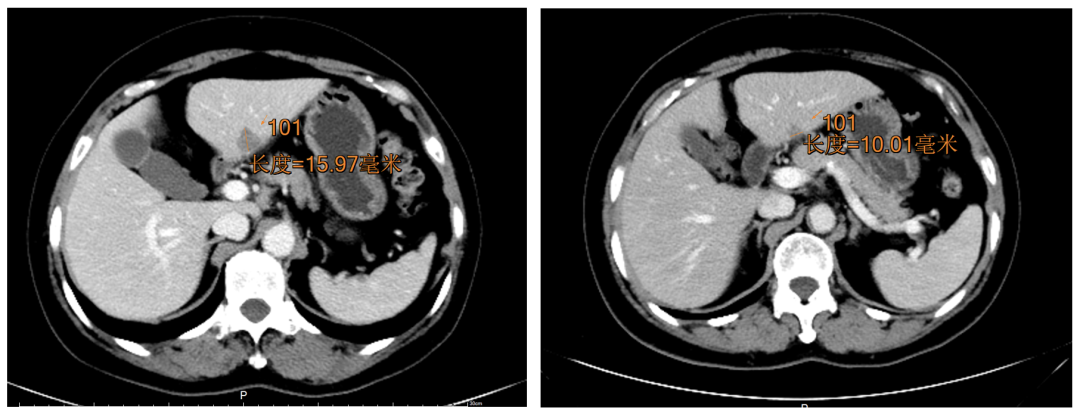

乳腺癌已取代肺癌,成为全球第一大癌症,严重威胁着女性生命健康。抗HER2治疗是HER2阳性乳腺癌患者的治疗基石,当前,如何克服耐药问题已成为研究者探索的重点。一项鸿运国际(中国)生物的新型抗HER2抗体药物偶联物(ADC)MRG002治疗HER2阳性晚期实体瘤的多中心、开放标签、剂量递增和扩大的I期研究正在如火如荼地召开。吉林大学第一医院吕铮副主任医师、贾琳主治医师收治的一例多线治疗后进展的HER2阳性晚期乳腺癌患者,经MRG002治疗仅2周期,肝转移灶从由15.97 mm缩小至10.01 mm,评估为部分缓解(PR)。治疗期间患者耐受性好。

综合评估患者,ECOG评分为1分,具有符合RECIST v1.1定义的可测量病灶,并符合所有入组标准,于2021.4.20签署知情同意书,2021.5.10入组接受MRG002治疗。患者基线期多发转移(肺转移、肝转移),2021.6.21治疗第2周期时进行了第1次影像学评估,发现肝转移灶由15.97 mm缩小至10.01 mm(图1)。评估为PR。同时患者治疗期间耐受性好,不良反应多为1级。